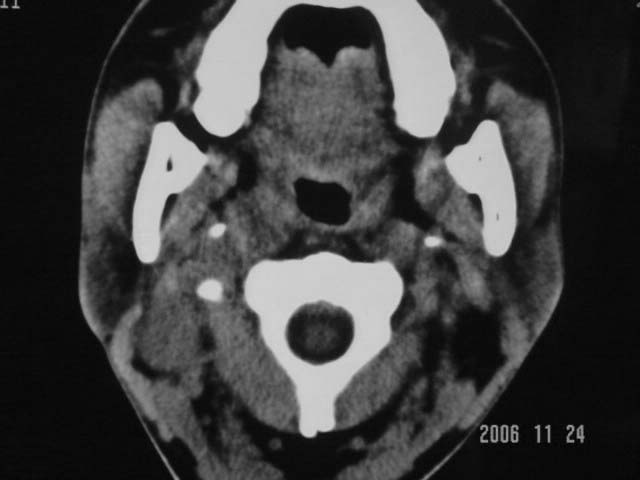

标题: CT5388:鼻塞、耳鸣3个月,涕中带血2周,颈部可触及肿大淋 [打印本页]

右侧鼻咽部软组织肿块,颅底骨质破坏,右侧颈部淋巴结肿大;诊断:鼻咽ca、右颈部淋巴结转移、颅底侵犯

右侧鼻口咽侧后壁不规则增厚,内可见密度不均匀性椭圆形软组织块影,边界欠清,咽旁间隙尚清.右颈部可见圆形软组织块影,鼻塞、耳鸣3个月,涕中带血2周,颈部可触及肿大淋巴结,考虑鼻咽癌,颈部淋巴转移.

右侧鼻咽后壁不规则增厚,内可见密度不均匀性椭圆形软组织块影,边界欠清,咽旁间隙尚清.右侧下方可见圆形软组织块影,双侧蝶窦呈均一高密度。

考虑:1、右侧鼻咽癌伴颈部淋巴结转移;

2、双侧蝶窦炎。

右侧鼻咽部软组织肿块,颅底骨质破坏,右侧颈部淋巴结肿大;诊断:右侧鼻咽ca伴右颈部淋巴结转移、颅底侵犯.

典型右侧鼻咽ca伴颈部淋巴结转移,中颅底骨侵蚀。

右侧鼻咽侧后壁不规则增厚,咽隐窝变钝,咽旁间隙变狭窄,见组织结节影[哨兵征],蝶骨似破坏,蝶窦内充塞软组织影,翼内外肌上分间隙模糊,右颈后三角区淋巴结肿大,右侧乳突增高气房消失。考虑鼻咽癌伴蝶窦侵犯及淋巴结转移,右侧浆液性中耳炎。其他恶性病变待排。